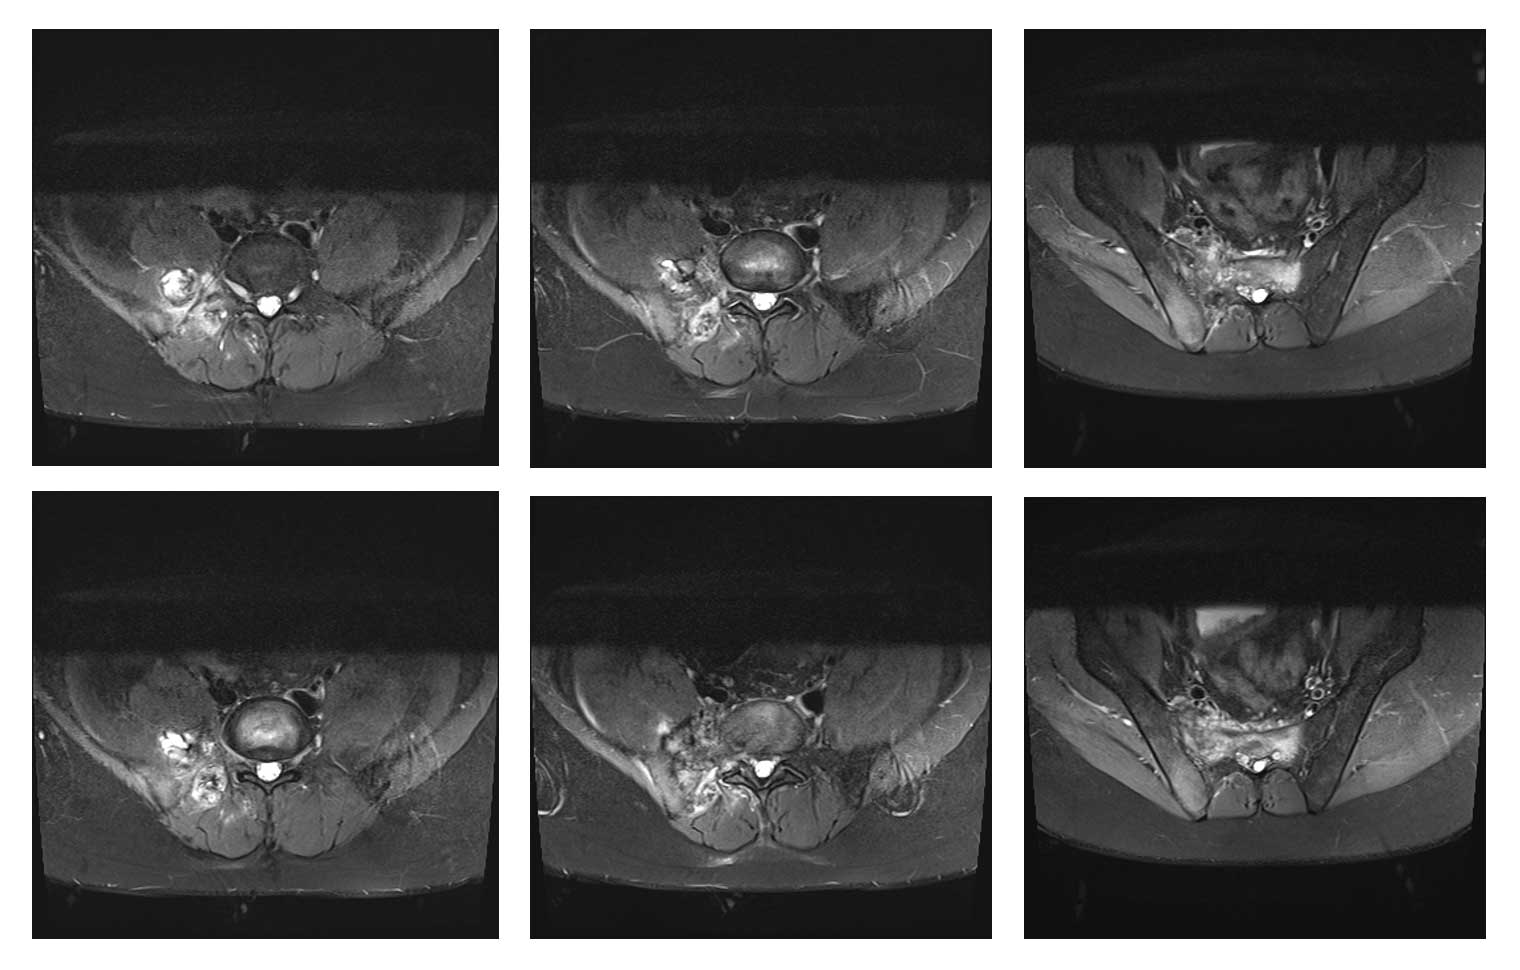

Ameliyat Öncesi: MR’da sağ iliak kanat posterior sakroiliak bölge üst kısım ve sakrumun tamamına yakınını kapsayan tümör dokusu ve çevreleyen ödem görülmekte.